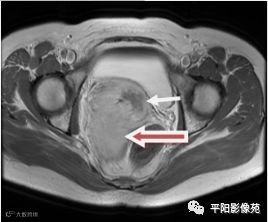

MRI表现

T1轴位

T2轴位

(宫腔内见金属节育环伪影)宫颈区见不规则形等T1稍长T2信号软组织肿块,DWI序列呈明显高信号,大小约为3.87cmX2.64cm,双侧宫颈基质低信号环连续性中断,病灶向子宫右后上方生长,周围脂肪间隙模糊,增强扫描明显强化,强化程度低于子宫及宫颈实质;子宫后方、子宫直肠间隙见不规则形长T1长T2信号软组织肿块,DWI序列呈高信号,大小约10.12cmX4.82cmX10.29cm,病灶呈分叶状,向下方生长与宫颈分界不清,与直肠分界尚清,增强扫描明显不均匀强化。